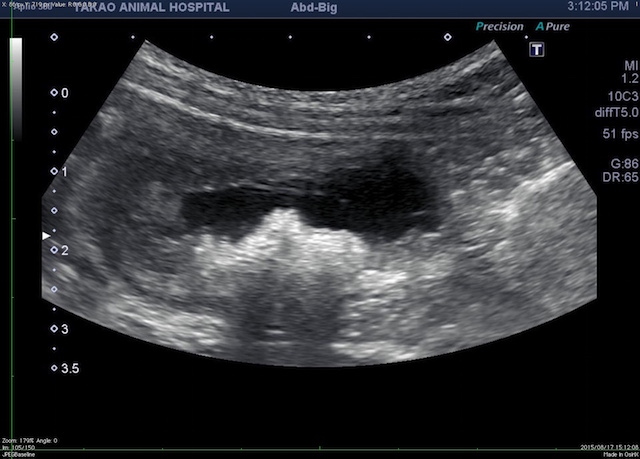

エコー検査にて膀胱炎と大量の膀胱結石が見つかりました。

【音響陰影が強く出ている部分が結石を疑う所見です。】